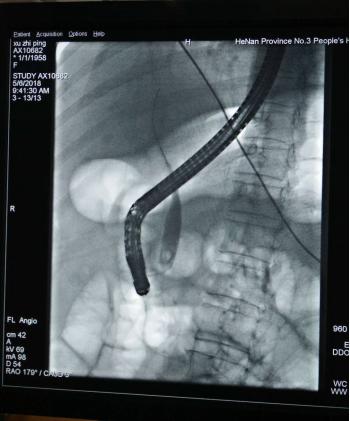

经内镜逆行性胰胆管造影术(ERCP)是指将十二指肠镜插至十二指肠降部,找到十二指肠乳头,由活检管道内插入造影导管至乳头开口部,注入造影剂后x线摄片,以显示胰胆管的技术。由于ERCP不用开刀,创伤小,手术时间短,并发症较外科手术少,住院时间也大大缩短,深受患者欢迎。在短短几十年中ERCP在临床上取得了巨大的成绩,已经成为当今胰胆疾病重要的治疗手段。

先行 ERCP 明确结石大小及分布,在内镜下小切口切开乳头括约肌,用取石网篮或托石网篮取出结石。十二指肠镜十分适用于胆总管结石的治疗,其适用对象范围广。乳头切开后,有利于胆汁引流,使结石不易再生复发。